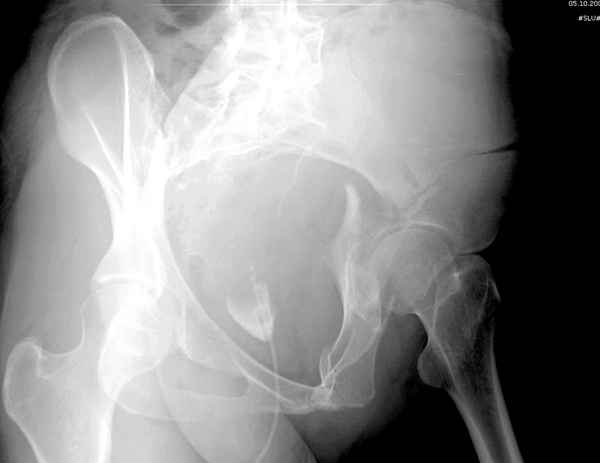

Все выступающие коллеги высказались насчет необходимости стандартных снимков по Judet, потому что для определения тактики лечения переломов вертлужной впадины 3Д снимки малоинформативны.

Летурнель разработал классификсацию на основании прямого, запирательного и подвздошного рентген снимков, котоые, кроме описания характера переломов, также подсказывают адекватный доступ для репозиции перелома.

Из того минимума, что представлено, мне кажется, мы имеем дело с двухколонным переломом вертлужной впадины. Обычно медиальный (центральный) "вывих" головки встречаются в сложных двухколонных переломах со смещением.

Здесь несколько вариантов двухколонных свежих переломов, которые были оперированы из одного-заднего, а также из двух: переднего и заднего доступов.